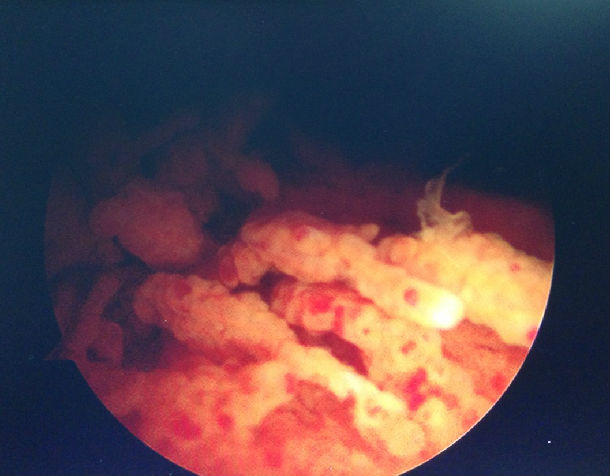

膝关节镜微创360度清理治疗色素沉着绒毛结节